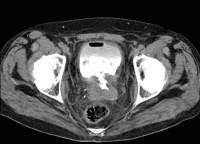

Рецидив рака шейки матки

Маточно-мочепузырный свищ